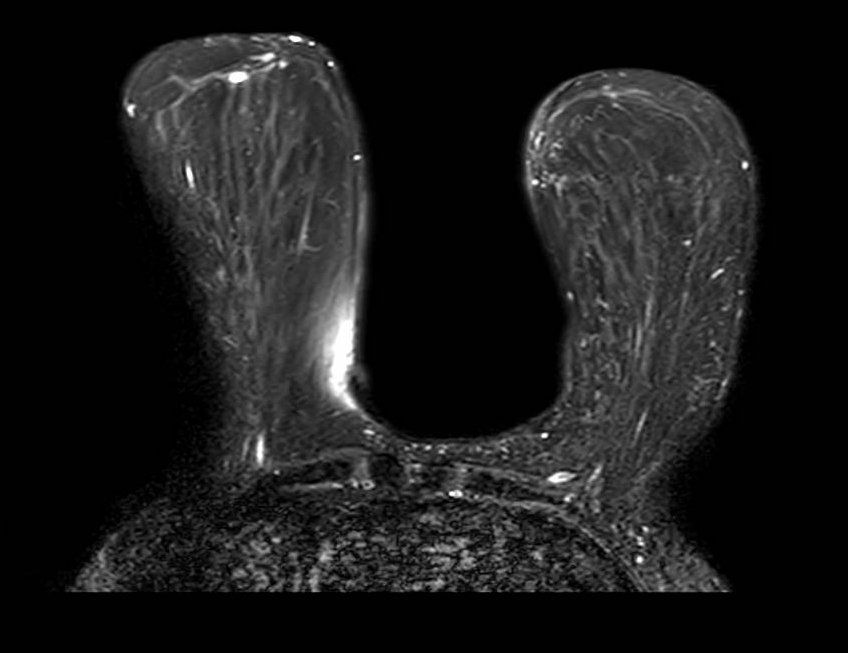

Fat Sat / B0 - T2

Bilateral asymmetric fat suppression failure on T2-weighted fat-saturated sequence. The pattern of inhomogeneous suppression differs between breasts, reflecting spatial variation in B0 across the imaging volume. Fat-saturated T2 sequences are particularly sensitive to field inhomogeneity given their longer echo times and narrower spectral selectivity.